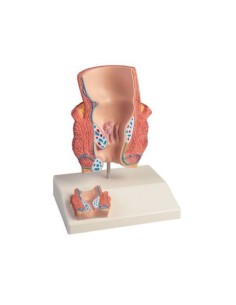

3B Modèle scientifique et anatomique : Pathologies de l'intestin K55